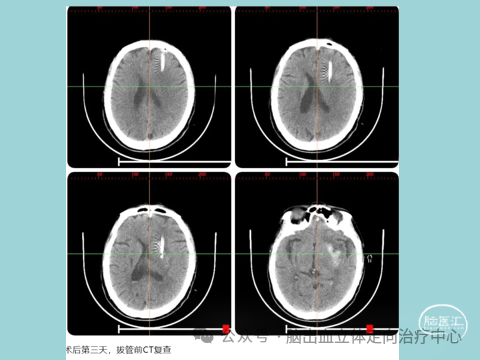

民权县人民医院神经外科开放床位80张,内设民权县颅脑创伤救治中心、脑出血研究所(脑出血微创治疗中心)、重症监护室。科室现拥有蔡司显微镜,西山神经内镜、Storz内镜成像系统、睿米神外及华科精准手术机器人、微创钻颅设备,蛇牌、西山等开颅设备,成功开展颅脑显微微创技术,立体定向脑出血微创钻孔、内镜手术治疗、神外机器人手术(睿米/华科)、成功应用3D Slicer、Mimics、E3D技术于临床。科室多人拥有神经创伤重症“5C”证及神经外科专科医师证书。

民权县人民医院神经外科.民权3D打印医学研究所全面开展数字神经外科临床技术应用、虚拟现实技术、多模态融合技术、3D打印穿刺导板等,可应用治疗高血压脑出血微创穿刺治疗,脑肿瘤术前精准定位、颅脑损伤手术治疗、脑卒中建设、3D打印临床教学及更精准的微创治疗、3D打印脊椎钉道手术、三叉神经痛微创治疗等,术前规划直观,手术治疗方便,术中缩短操作时间.....,科技结合临床,个体化方案,3D转化精准医学治疗!